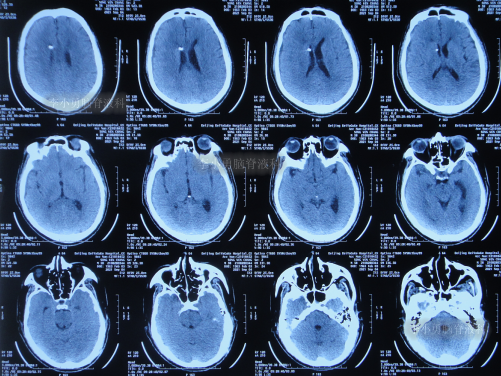

2022年1月25日(脑室腹腔分流术后15天)治好出院,出院时:神清气爽,走路完全正常(图-15);出院时头颅CT无异常(图-16)。

图-16:出院时头颅CT